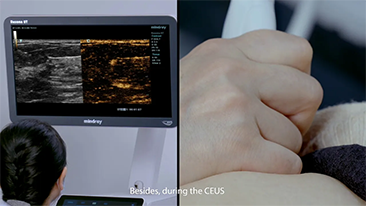

Wie deutlich k?nnen Sie eine Leber erkennen?

Bei fokalen Leberl?sionen wie H?mangiomen oder Leberkrebs spielt die Ultraschallkontrastdarstellung eine zentrale Rolle. Mit der weitreichenden nichtlinearen UWN+Kontrast-Bildgebungstechnologie k?nnen eine bessere Penetration, ein h?heres Kontrast-Gewebe-Verh?ltnis, eine geringere MI und eine l?ngere Beobachtung der Durchblutungsdauer erreicht werden.